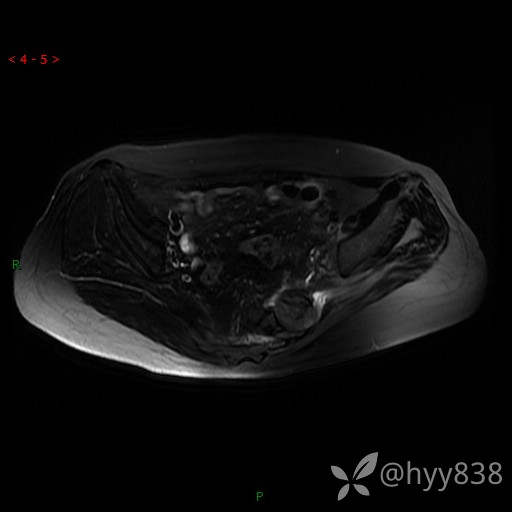

骨盆MRI平扫(T1WI+T2WI+DWI)(外院CT,不能上传)